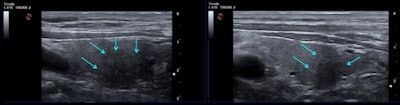

A 46-year-old man two to three months after COVID-19 infection. Thyroid ultrasound scan in transverse (left) and longitudinal (right) planes shows presence of focal hypoechoic area (arrows) suggestive of thyroiditis in left thyroid lobe, inferior and posterior position. All figures courtesy of Dr. Ilaria Muller, PhD, presented at ENDO 2021."When you perform the first ultrasound in sub-acute thyroiditis, you've got the big hyperechoic areas, then you usually start steroid treatment and despite the neck pain disappearing, when you repeat the ultrasound after one month, two months, the areas are still there and they take months to disappear," She said.

Bearing in mind such behavior of classic subacute thyroiditis, she said she did not find it surprising that hypoechoic areas of atypical thyroiditis related to COVID-19 also persisted after two to three months. Furthermore, the whole thyroid gland was a little more dishomogeneous and showed a diffusely hypoechoic pattern compared to a normal thyroid, although she said it was quite difficult to standardize in the ultrasound machine settings.